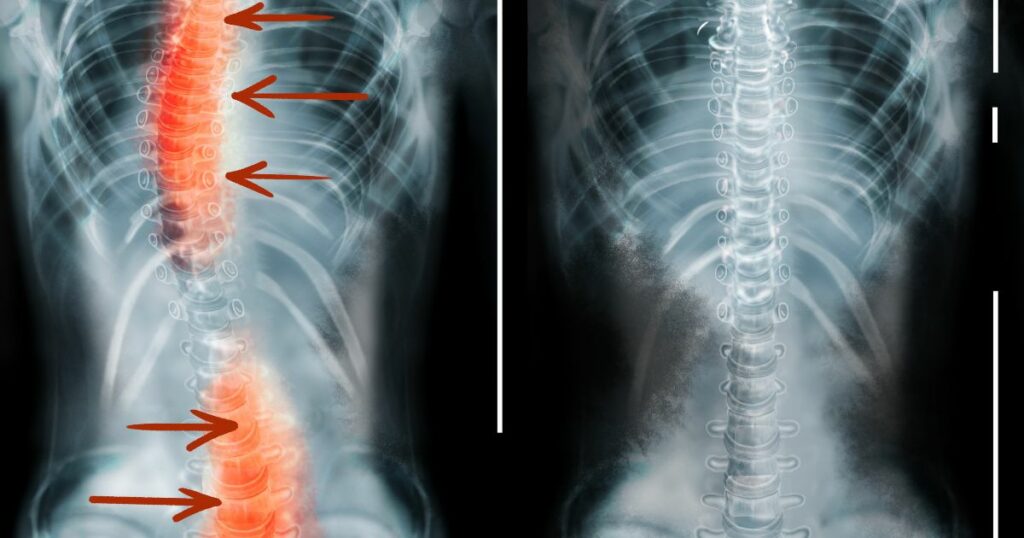

Scoliosis causes an abnormal curvature of the spine, which can be either “C” shaped or “S” shaped.

But it’s not just any curve. In scoliosis, the spine twists and turns in three dimensions. This means it’s not just a curve to the side, but the spine also rotates.

To diagnose scoliosis, a doctor will typically perform a physical examination and may order diagnostic tests such as X-rays, MRI, or CT scans.

During the physical exam, the doctor will look for signs of curvature in the spine, such as uneven shoulders or hips. They may also ask the patient to bend forward to see if there is any visible curvature in the spine.